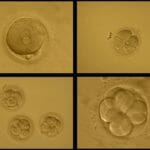

Early Embryo Development